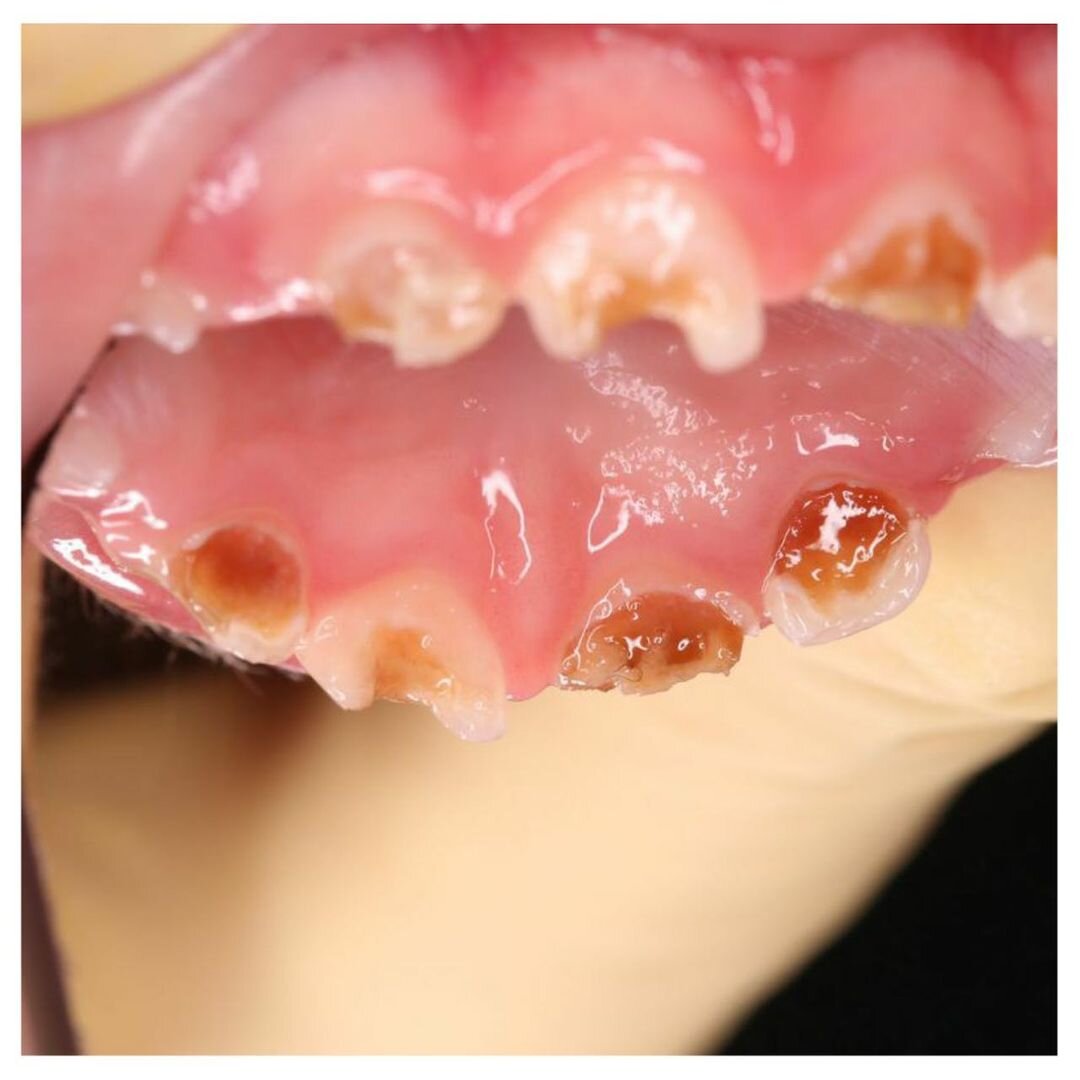

Пришла мама с малышом (1 г 10 мес).

В августе его лечили под наркозом в другой клинике.

Были вылечены, внимание❗ Только 3 жевательных зуба❗

Врач не трогал передние и сказал, что лечить их не нужно, пусть гниют, а когда появятся свищи, тогда и удалите...

В полости рта маленького пациента остались разрушенные, пораженные кариесом, зубки.

Это постоянный очаг инфекции!

Воспаление может распространиться вглубь, поразить периодонт и зачатки постоянных зубов!

На приеме мы сделали снимки — лечить нужно срочно.

Центральный верхний резец под вопросом: удалять или еще можно спасти.